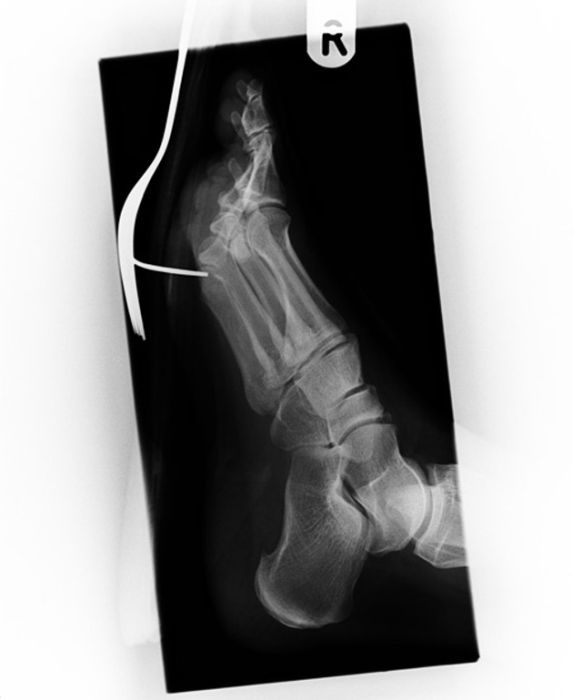

Рентгеновские снимки людей, которые умудрились сами или с чужой помощью разместить внутри своего организма разные посторонние предметы. От вилок и ножей до пуль и бензопилы (!!!). По этическим соображениям обычные снимки таких травм и повреждений выкладывать нельзя, зато рентгеновские можно – на них травмы видны достаточно условно, хоть и очень понятно.